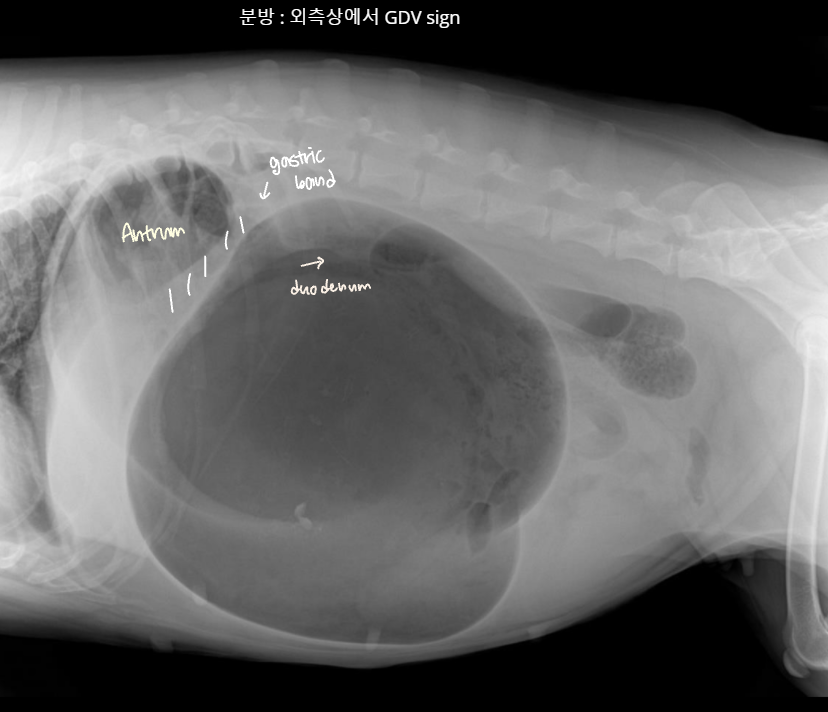

์ํ์ฅ : GD vs. GDV

- ๊ฐ๋ณ์ key point๋ pylorus์ ์์น & ์์ ๋ถํํ(compartmentalization) !

- ์ ์์ ์ธ ์์น๋ ์ธ์ธก์์์ ์๋์ชฝ, ๋ณต๋ฐฐ์์์ ์ผ์ชฝ์ ์์น.

- GD๋ ์๊ฐ ํ์ฅ๋์ด ์์ผ๋, ์์น๋ ๊ทธ๋๋ก.

- GDV๋ ์ฅ์ด ๊ผฌ์ด๋ฉด์ ์์น๊ฐ ๋ฌ๋ผ์ง๋ฏ๋ก, pylorus์ ์์น๊ฐ ์ธ์ธก์์์ ์์ชฝ

| GD | GDV | |

|---|---|---|

| VD | - greater curvature ์ผ์ชฝ(์ ์) * 360๋ ํ์ ์์๋ ์ผ์ชฝ์ ์์น | - greater curvature ์ค๋ฅธ์ชฝ (180๋ ์ผ์ ) - duodenum ์์น๋ ํจ๊ป ๊ผฌ์ |

| RL | - pylorus๊ฐ ์๋์ชฝ(์ ์) | - pylorus ์์ชฝ - ์์ ๋ถํํ(compartmentalization) : ๋ถ๋ฐฉ ํ์ธ - gastric band (soft tissue) ๊ด์ฐฐ |

![]() ![]() | ![]() ![]() | |

[๋ถํํ]![]() ![]() |

GDV

- ๋ฐฐ๊ฐ ๋นต๋นตํ๊ณ , ๊ณ ํต์ค๋ฌ์ ํ๋ฉด์ ๋ด์ํจ.

- ๋ํ๊ฒฌ์์ ์ ๋ฐ์ํจ. ์๊ธ ์์ ํ์.

- Serosal detail ๊ฐ์, ํ์ alveolar/interstitial pattern์ด ํจ๊ป ๊ด์ฐฐ๋๋ฉด ์ํ๊ฐ ์ ์ข์.

- thromboembolism, ํํฌ ๋ด ์ถํ ๊ฐ๋ฅ์ฑ.. โ DIC๊น์ง ์ด์ด์ง.